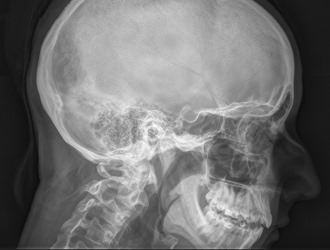

Диагностика корешкового синдрома осуществляется с помощью рентгенографии. Основным методом для выявления сжатия нервных корешков спинного мозга является рентгенографическое исследование. Врач назначает пациенту сделать снимки позвоночника в двух проекциях: фронтальной и боковой.

Полученные изображения позволяют оценить расстояние между позвонками и определить место, где происходит сжатие нерва.

В некоторых случаях может быть рекомендована магнитно-резонансная томография. Этот метод диагностики предоставляет более полную информацию по сравнению с рентгенографией, однако его стоимость значительно выше.

Использование магнитно-резонансного томографа дает возможность получить изображения, на которых видны не только позвонки, но и нервные окончания, корешки и сосуды.

На основании таких снимков можно установить более точный диагноз. Тем не менее, из-за высокой цены на этот вид диагностики не каждый пациент может позволить себе его пройти.